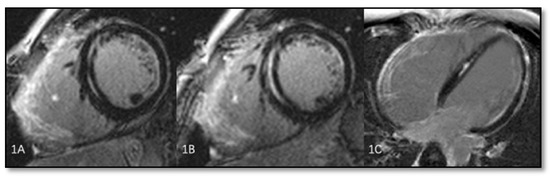

- Intramyocardial adipose tissue disposition—”obsolete”Although intramyocardial fat has long been a diagnostic criterion for ARVC, it is no longer used because other pathological or physiological conditions can lead to this appearance in cardiac MRI. In normal people, epicardial fat can penetrate to the myocardium and endocardium, with no clear demarcation between the epicardium and the myocardium, leading to misinterpreted images as ARVC. When intramyocardial fat is detected, it will be considered pathological only if it is associated with contraction abnormalities of the corresponding wall [12,45].Fat in ARVC appears as hyperintense intramyocardial signal at T1 spin-echo. Adipose tissue infiltrates mainly the RVOT, the free wall of the right ventricle, the intracavitary trabeculae, the moderating band, and the right side of the interventricular septum (Figure 4).Tansey et al. showed on autopsies of individuals without known heart disease that 85% of them had myocardial infiltrates with adipose tissue [46]. Mainly, the RVOT, free wall of RV wall, apex, and RV antero-lateral wall are affected, but these intramyocardial deposits do not change the thickness of the ventricular wall or the regional contraction. If the deposits extend from the epicardium to the endocardium, crossing the myocardium, then the ventricular wall may increase in size as a normal feature of the adipose distribution. It seems that these fat deposits in healthy people increase with age and are more common in obese people without being pathological [47].